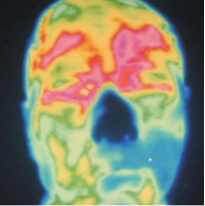

红外热成像技术在脑卒中预防筛查的应用中,可客观地反映脑部能量的变化,根据脑部热量分布评估脑部寒热是否平衡,根据脑部经络穴位热量分布评估脑部气血是否阻碍,利用能量热图评估其健康度,更可对脑卒中进行筛查,提前半年预警。

脸部热像图显示前额右侧和眼睛(图像左侧)异常凉区。这种热信号暗示动脉畸形或动脉变窄或变硬,这表明可能发生中风。